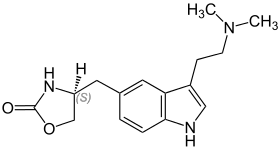

| Zolmitriptan | artificial | 5-(CHNHC=OOCH2) | CH3 | CH3 | 5-( 4-(S)-1,3-oxazolidin-2-one)-N,N-dimethyltryptamine | 139264-17-8 |